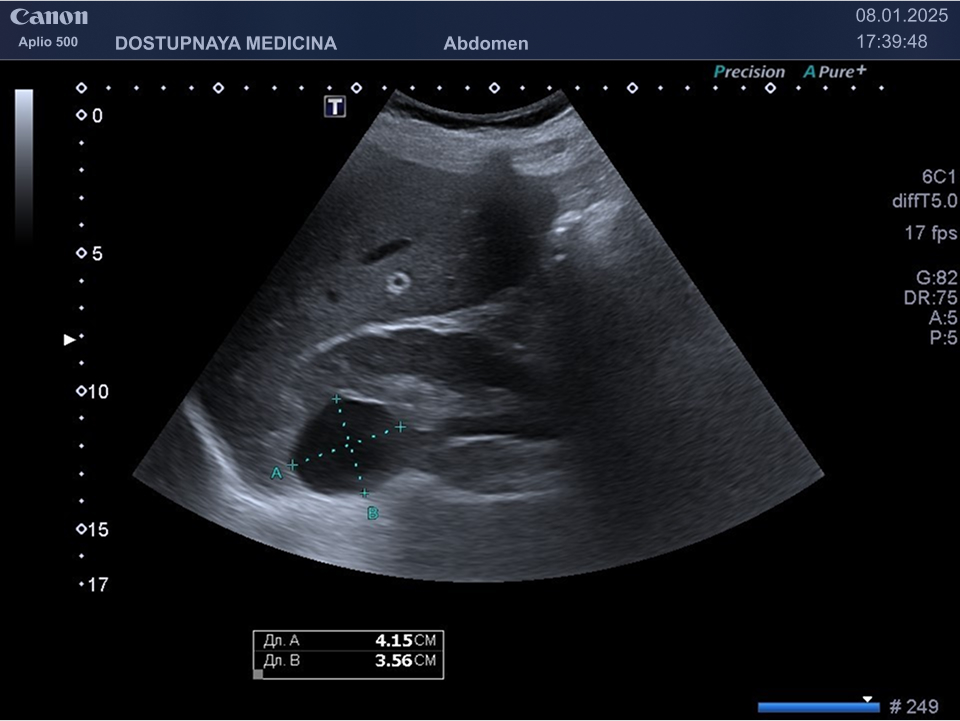

- синусные кисты почек, которые находятся в области ворот почки и лоханки

Кисты небольших размеров (до 3 см), как правило, не требуют никакого лечения, необходимо лишь контролировать размеры и количество кист не реже 1 раза в 6-12 месяцев. Кисты от 3 до 5 см можно пунктировать и дренировать под контролем УЗИ с последующим введением в них склерозирующего препарата. Более крупные кисты (больше 5 см), как правило, иссекают лапароскопически. Медикаментозного лечения кист на данный момент не существует.

Существует классификация кист Bosniak по степени онкологической опасности:

- Bosniak 2 – киста с перегородками и толщиной стенки 3мм или простая киста больше 3 см, требует наблюдение 1 раз в 2 месяца